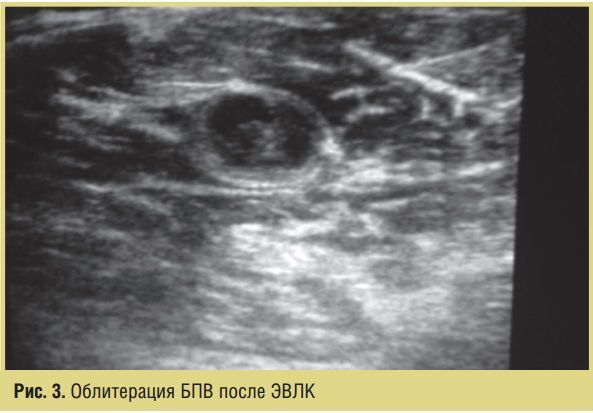

Перевязки проводились с обязательным УЗИ-контролем состояния целевой вены после процедуры ЭВЛК для верификации ликвидации вертикального вено-венозного рефлюкса как источника декомпенсации венозного кровообращения (рис. 3).